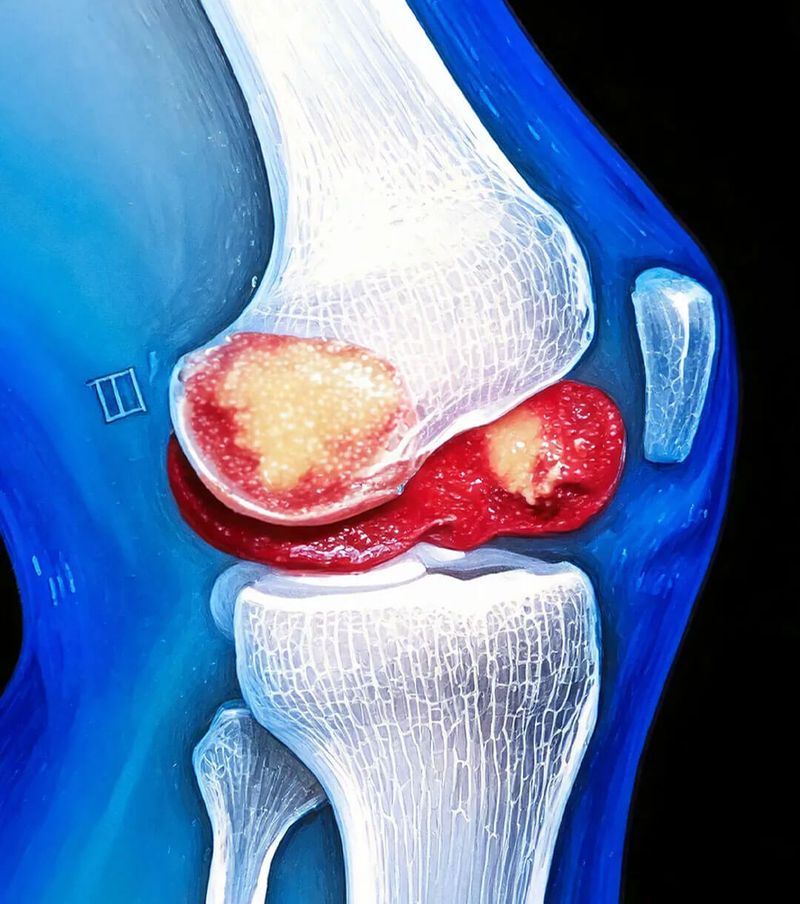

Menopause is more than just a phase of change. It affects almost all processes in your body – often with consequences that only become visible gradually. During this period, your joints are put under extra strain. One important cause of this is the so-called waste barrier that forms in the joints. But what exactly does that mean and how does it arise?

X-Factor Waste Barrier: When Your Joint Becomes a Trap

Under normal circumstances, your body cleanses itself.

With every movement, waste products are created in our joints. This is similar to the exhaust fumes produced by a running engine.

These microscopic particles accumulate in the joint space and can cause inflammation and pain. When the body is healthy, these waste products are removed via the synovial fluid.

But during menopause, the composition of this fluid changes!

The result:

The waste products remain in the joint and irritate the sensitive tissue. Over time, a vicious cycle of inflammation and further deposits develops.

During menopause, this system suddenly stops functioning as it should.

Instead, the waste products build up as sediment in the joints.

They form a real barrier, comparable to a clogged filter.

This 'waste barrier' has two problematic consequences:

On the one hand, it itself causes irritation and inflammation.

On the other hand, it blocks access to important nutrients that the joint urgently needs for its regeneration.

The joints are, as it were, pinched on both sides: they can no longer remove waste products or absorb new nutrients.

This strain makes your joints painful, stiff and they wear out faster.